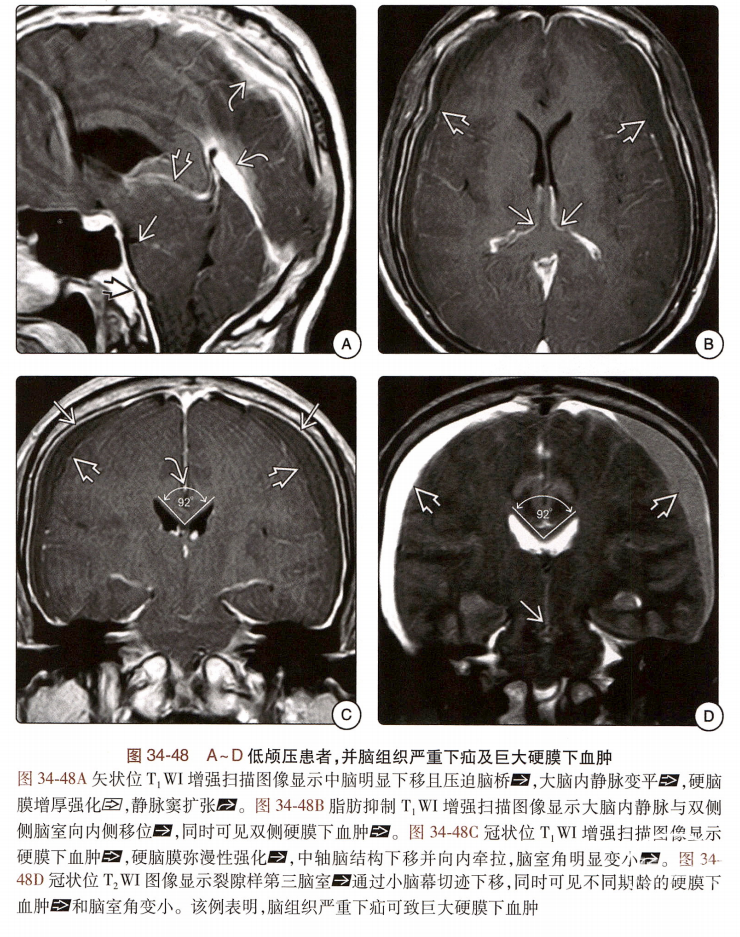

低颅压综合征